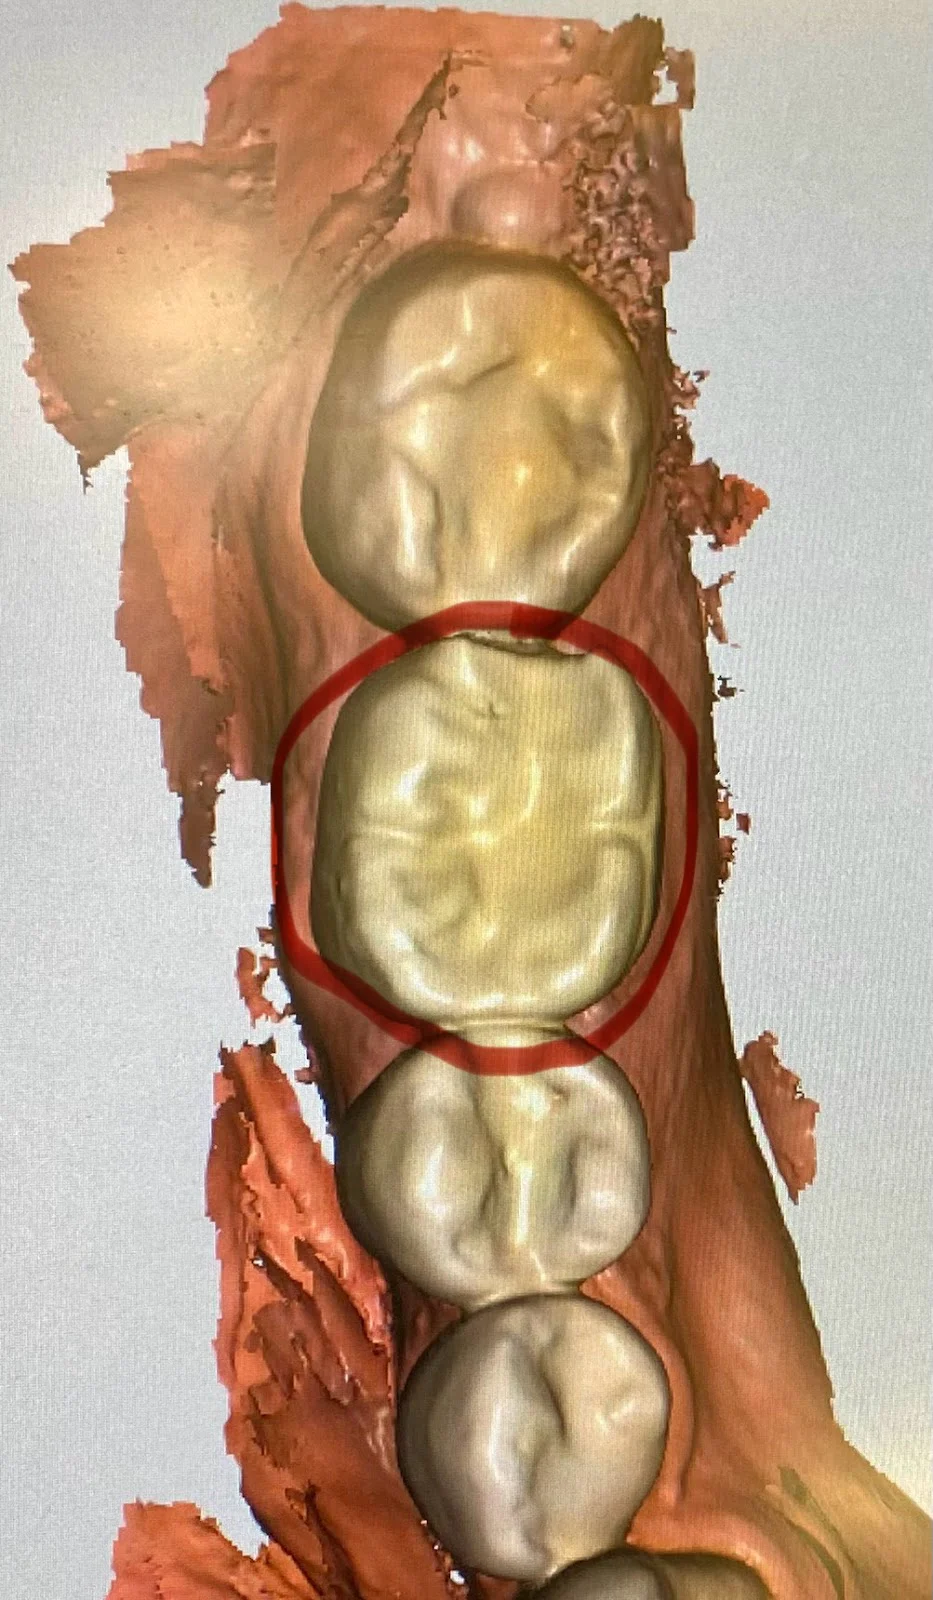

Great Smiles Family Dental Photos